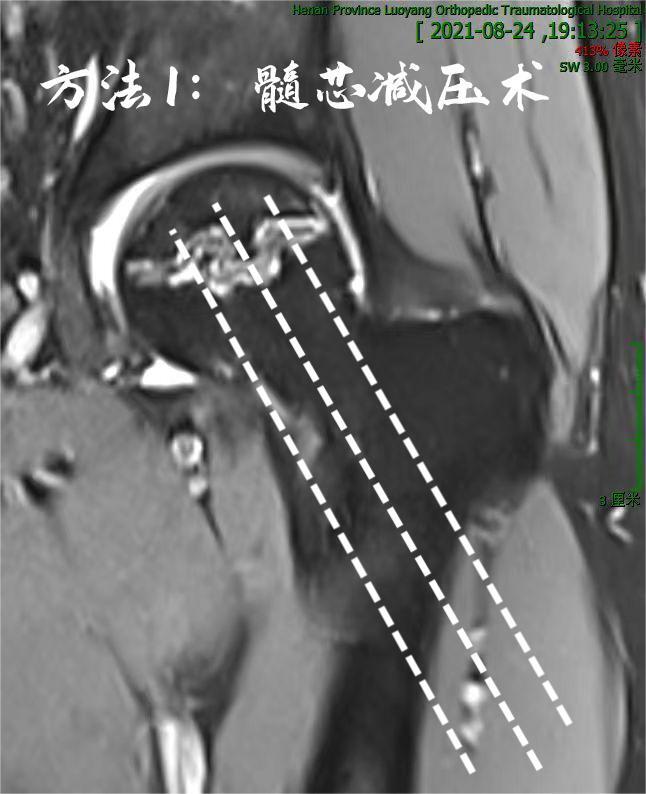

我们以一例常见病例探讨如何应对:

男性,46岁,股骨头坏死2期:

1. 传统方法可以行髓芯减压术,简单、微创,术后2~3天即可出院:

2. 也可以行微创减压植骨术,刀口约2cm,术后6天可出院:

3. 当然,有条件的也可以行体外冲击波治疗,无创不手术,一周内见效,不影响工作,日常生活照旧,无需卧床休养、拄拐保护:

作为国内较早成立的股骨头坏死专科,我们采用了上述第3种方法,辅以中西药物治疗,患者无需长期卧床、拄拐,边工作边治疗,很快症状得到缓解,复查资料如下:

与治疗前比较,磁共振显示的“ 双线征 ”信号减弱、宽度变窄,再继续观察、间断治疗,股骨头无忧矣!